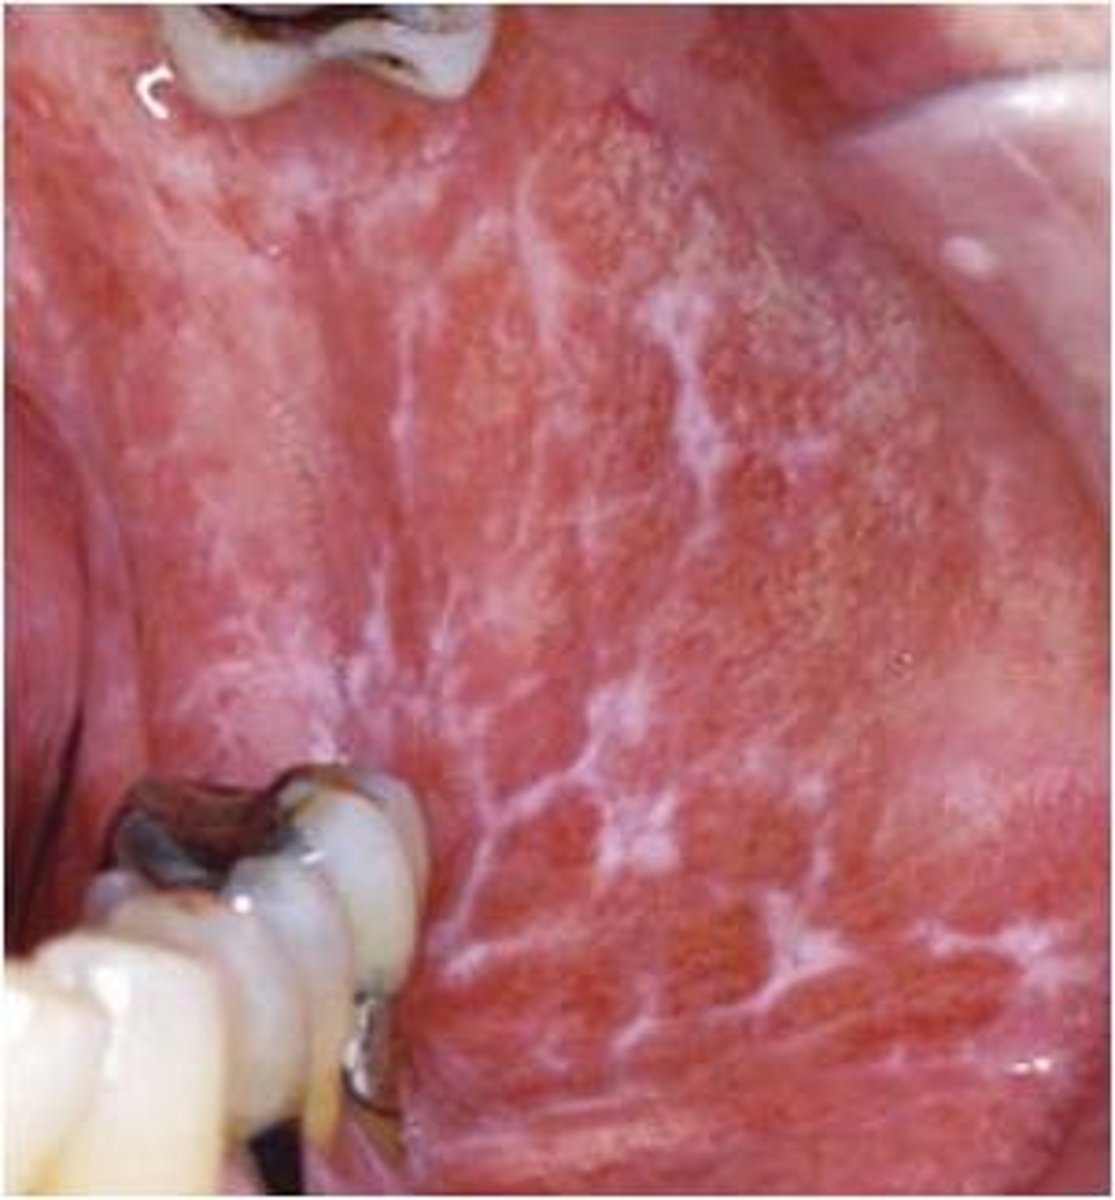

lichen planus

diagnose this image

Purple (Violaceous), Polygonal, Pruritic, Papule w/ fine white lacy lines